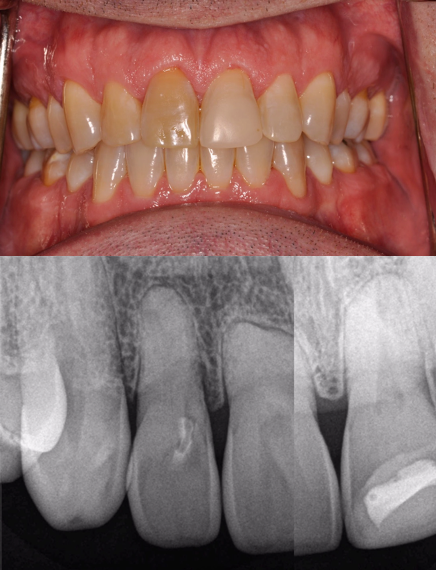

Figure 10 shows a classic high-risk esthetic case. A 19-year-old female patient with a thin gingival biotype presented with a congenitally missing tooth No. 10. She had previously undergone clear aligner therapy to improve the esthetics of her teeth to the extent possible. The clinician discussed options with her: a bonded Maryland Bridge, a three-unit fixed prosthesis, or implant placement. The patient desired a dental implant with an immediate provisional. It was decided that placement of an implant would require a hybrid workflow-ie, analog technology as well as digital technology using dynamic navigation. Figure 11 shows an imaging guide that can be used in such a case, as well as a virtual tooth.

To measure accuracy, the clinician superimposed the plan on the postoperative CT scan and then measured the difference with software. This case had an angular deviation of 3.1°, a platform deviation of 0.81 mm, and an apical deviation of 0.45 mm-all of which were within acceptable parameters.

Figure 12 shows the temporary abutment (left panel) after the implant and connective tissue graft were placed, and the patient 2 weeks postoperatively (right panel). Seven years later, the restoration remains sound (Figure 13).

Figure 14 through Figure 18 show a partially dentate patient for whom a fully digital workflow was utilized. This 47-year-old male presented with root blunting and mobility of teeth Nos. 7, 8, and 9 (Figure 14). A thermoplastic clip was attached during the CBCT, and an intraoral scan was taken and superimposed on the CBCT. The case was then planned in the navigation planning software (Figure 15). Once the teeth were extracted, intraoral scanning was performed. The intraoral scan was imported into lab software (Figure 16), and a PMMA milled screw-retained prosthesis was fabricated. The prosthesis was placed the next morning (Figure 17). Two months later, a new intraoral scan was taken to capture the mature soft tissue, and the final milled titanium abutment and restoration were delivered (Figure 18).

Fig 10. Patient with congenitally missing tooth No. 10.

Fig 11. Virtual tooth and imaging guide that were used for planning in this patient with the congenitally missing tooth No. 10.

Fig 12. Left panel: temporary abutment in the patient with the congenitally missing tooth No. 10. Right panel: Two weeks postoperatively after the implant and connective tissue graft placement. (Images courtesy of Dr. Keith Progebin.)

Fig 13. Patient with congenitally missing tooth No. 10 at 7 years postoperatively.

Fig 14. Preoperative view of a partially dentate case. Patient with root blunting and grade 3 mobility.

Fig 15. The case was planned using navigation planning software in this same patient.

Fig 16. Virtual design of the provisional prosthesis.

Fig 17. Views of the milled PMMA screw-retained provisional restoration. Note the screw access holes in the incisor edges (left panel). (Images courtesy of Dr. Kim Knoll.)

Fig 18. Placement of the final prosthesis. Milled titanium abutments (left panel) and Emax crowns (right panel). (Images courtesy of Dr. Kim Knoll.)